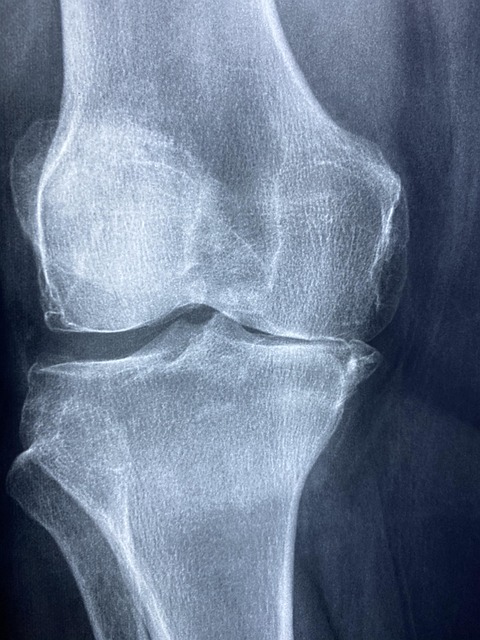

2025.04.29 - [건강하게 오래 살기] - 🔍골반 불균형에 의한 무릎 통증 _ 척추 측만증 무릎 통증 연관성🦵

🔍골반 불균형에 의한 무릎 통증 _ 척추 측만증 무릎 통증 연관성🦵

🙋♀️ 등산후 무릅통증이 심해져, 병원을 다닌지 어느덧 5개월이 지났어요. 제가 겪은 무릎 통증과 생각한것에 대해 이야기해보려고 합니다. 특히 무릎 통증과 골반 불균형의 연관성에 대해